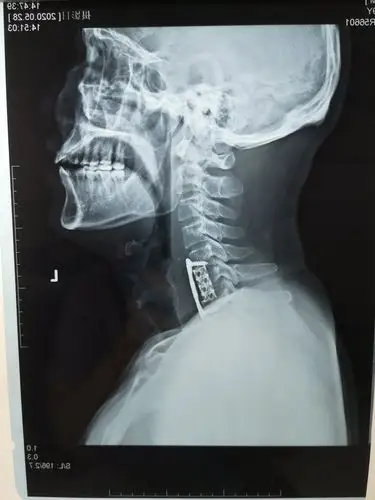

颈椎侧位-x线片- 解剖图片 @medsci

颈椎侧位片请分析一下.急...... - 医学影像学讨论版 - 爱爱医医学论

颈椎病例 (附x ct图) - 医学影像学讨论版 - 爱爱医医学论坛

颈椎图片,求解,谢谢! - 骨科与显微外科专业讨论版 - 爱爱医医学论坛

多节段退变性颈椎病的颈前路钢板固定手术治疗 - 美篇